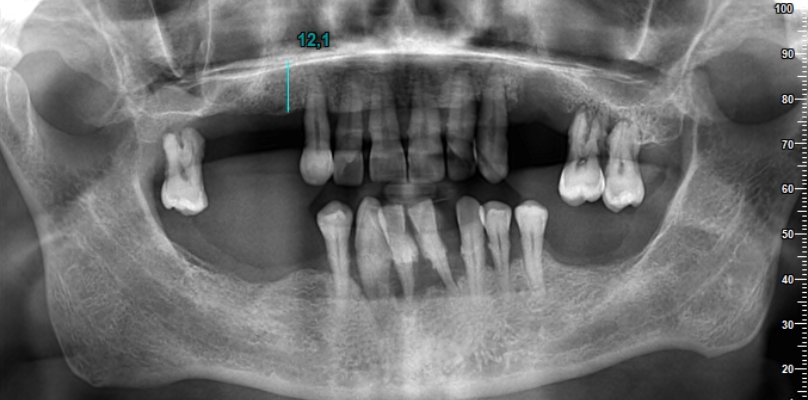

La première étape du processus de traitement consiste à prendre des images radiographiques détaillées. Ces images aident à déterminer le plan de traitement le plus approprié en évaluant la structure de votre mâchoire et votre santé dentaire. Nos radiographies révèlent à quel point le processus de traitement est extrêmement minutieux.